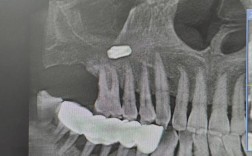

- 评估是关键: 术前必须通过临床检查和影像学评估(如CBCT)精确测量骨量,制定个性化的增量方案。